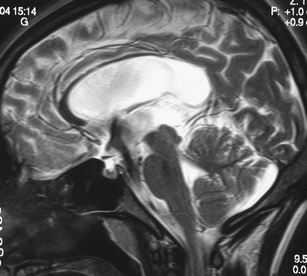

The sylvian aqueduct is the most common site of intraventricular blockage of the cerebro-spinal fluid. Clinical aspects, neuroradiological appearance, and treatment of hydrocephalus secondary to aqueductal stenosis are specific.

The correct interpretation of the modern neuroradiologic techniques may help in selecting adequate treatment between the two main options (third ventriculostomy or shunting). In the last decades, endoscopic third ventriculostomy has become the first-line treatment of aqueductal stenosis; however, some issues, such as the cause of failures in well selected patients, long-term outcome in infant treated with ETV, and effect of persistent ventriculomegaly on neuropsychological developmental, remain unanswered.